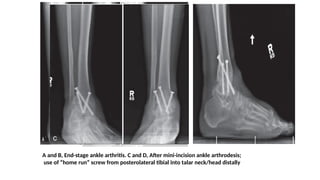

A and B, End-stage ankle arthritis. C and D, After mini-incision ankle arthrodesis;

use of “home run” screw from posterolateral tibial into talar neck/head distally

A and B,End-stage ankle arthritis. C and D, After mini-incision ankle arthrodesis; use of “home run” screw from posterolateral tibial into talar neck/head distally